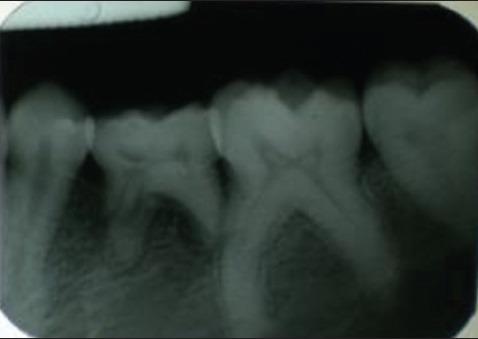

Buccal mucosal hypertrophy secondary to open bite.